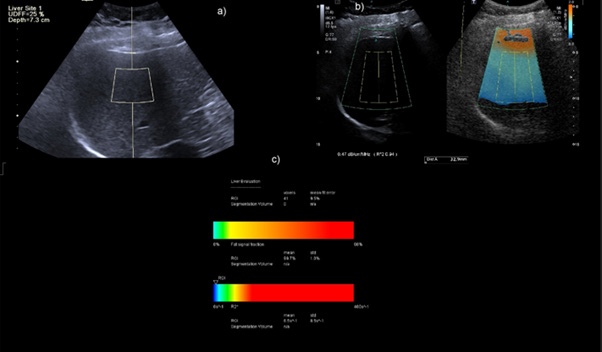

Figure 3: Concordant case of Category S2 grade patient on Aplio showing ATI of 0.76db/cm/MHz b) UDFF of 17% in the same patient.